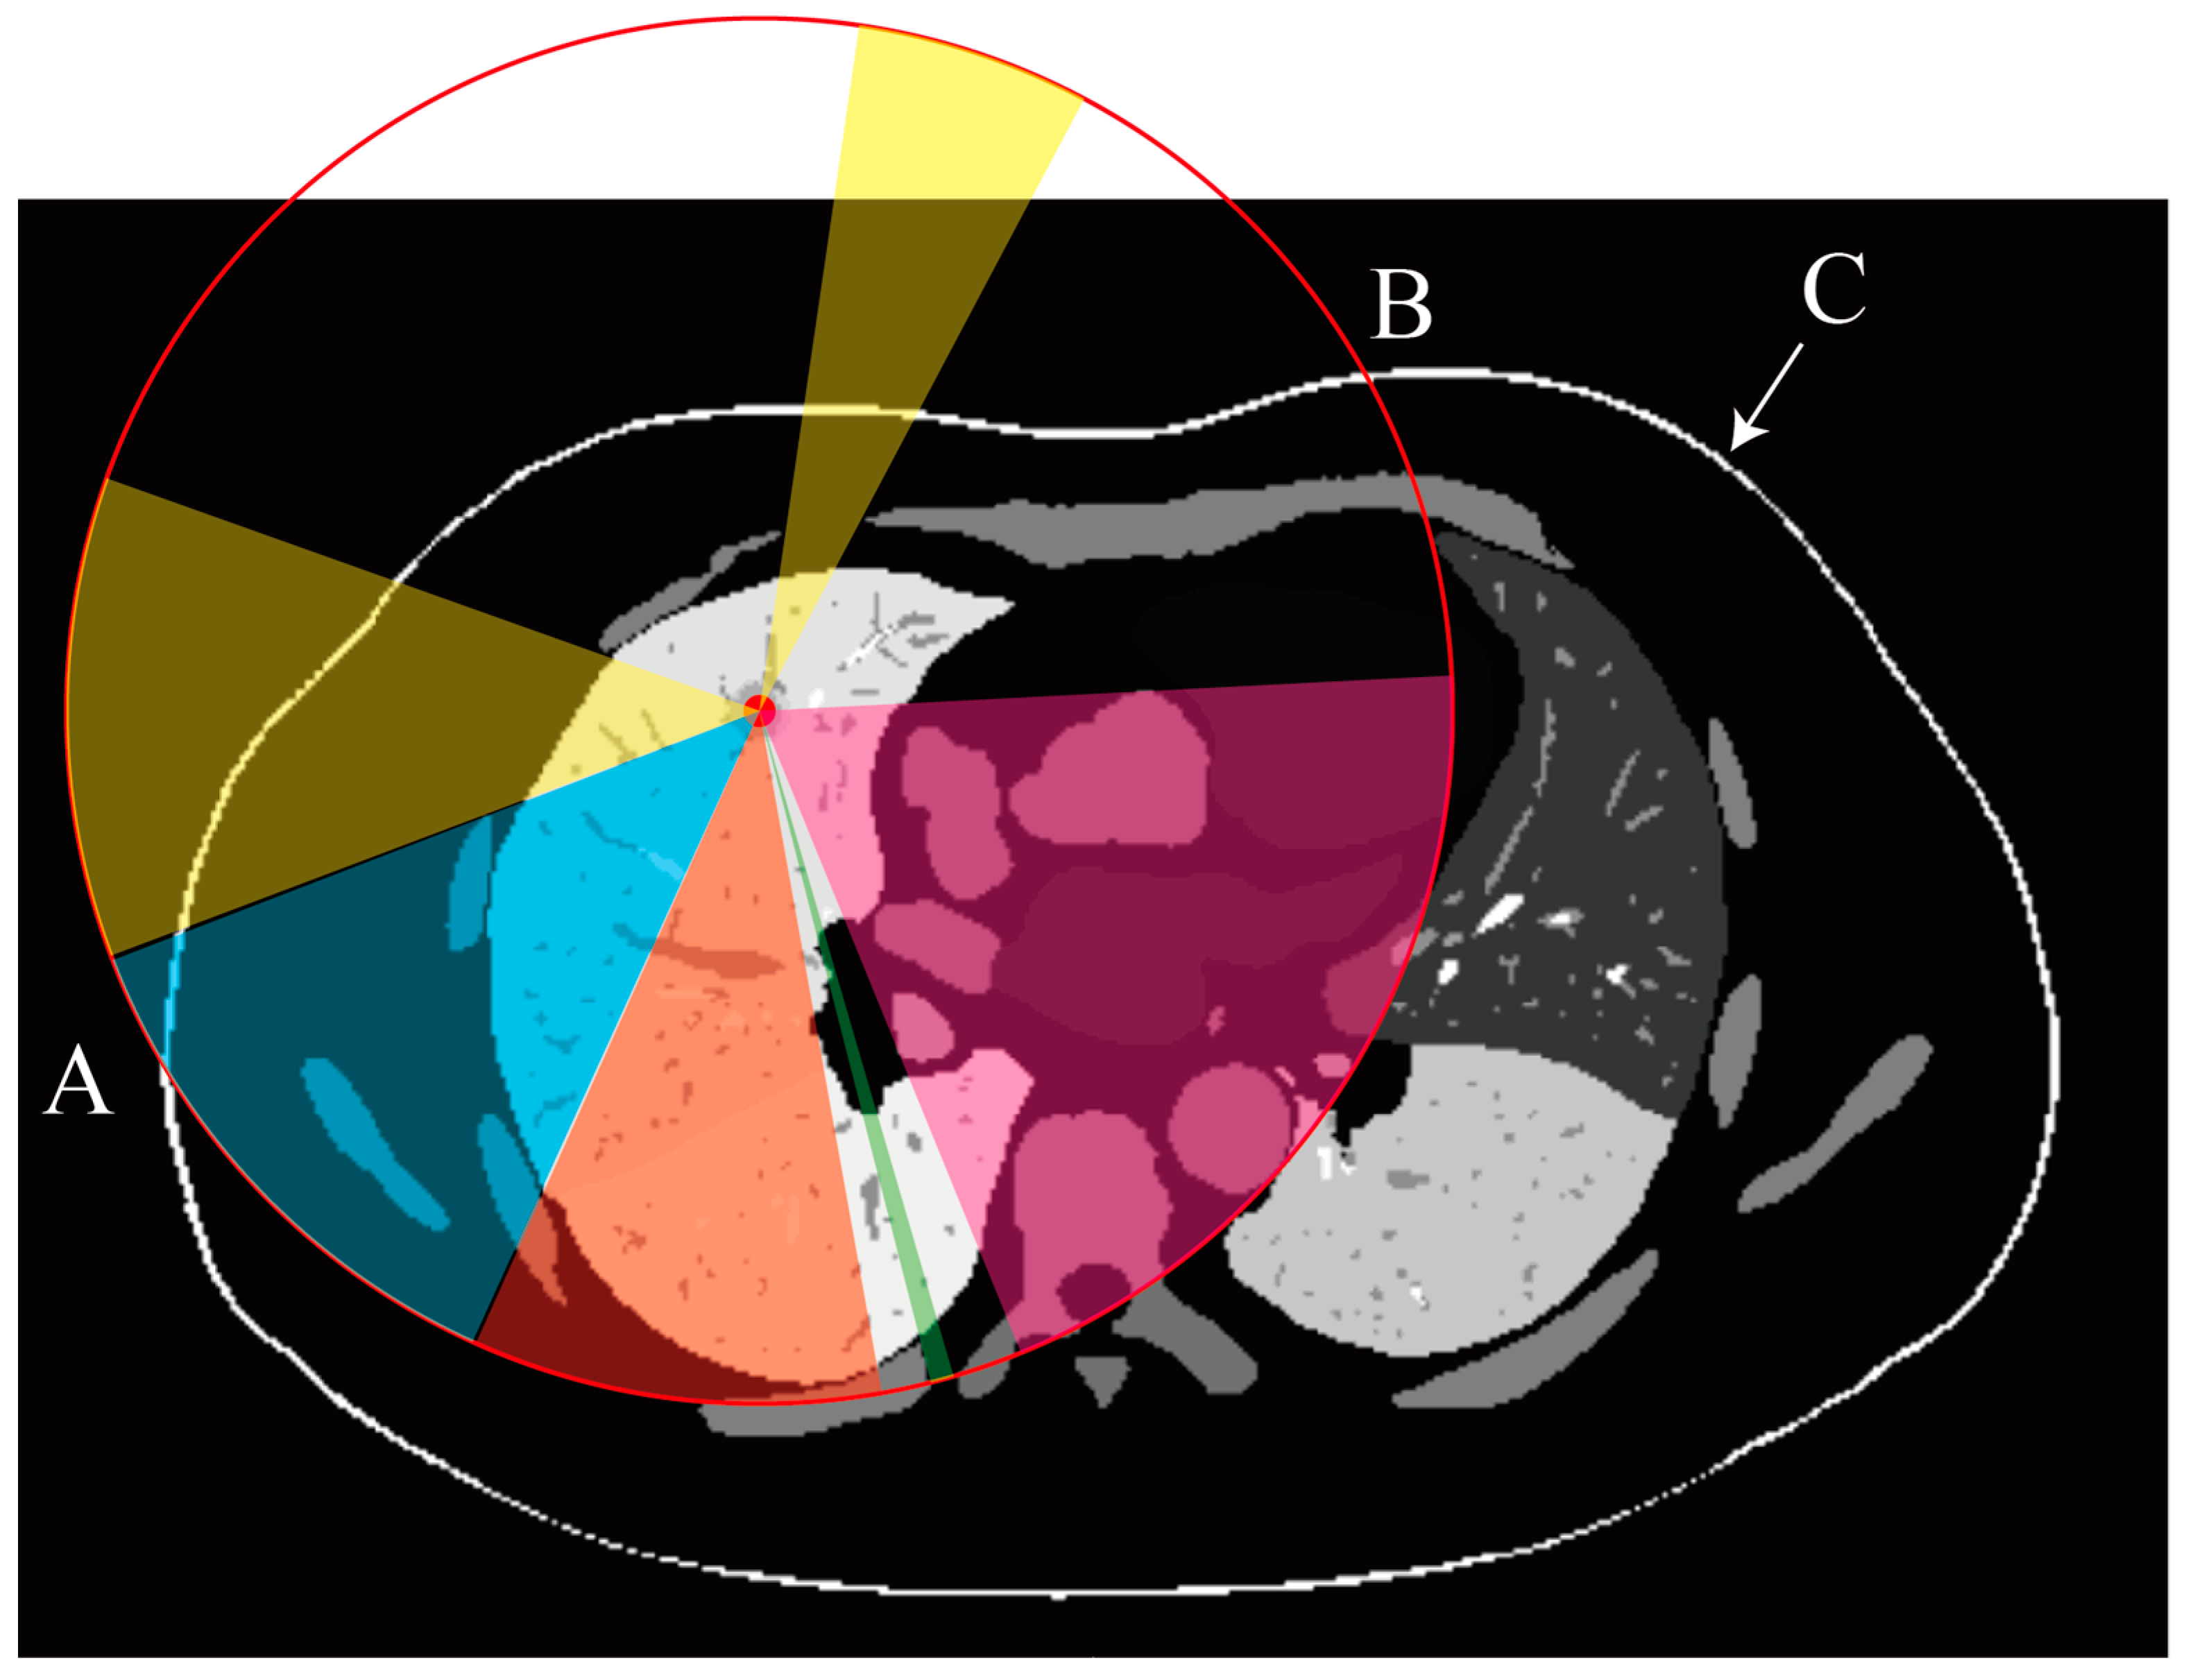

Figure 2 presents a 2D cross-sectional view of a region containing potential puncture paths. Grayscale values indicate the segmentation labels for different organs or tissues. The red point marks the puncture target, and the red circle represents a sphere with a radius corresponding to the length of the biopsy needle (R). Feasible puncture paths are constrained to lie within the region between points A and B, ensuring that the needle can reach the target. The colors represent various constraints: yellow indicates feasible areas, blue indicates areas obstructed by the rib, orange denotes regions where the needle would cross multiple lung lobes, green signifies insufficient needle length, and pink highlights areas blocked by the heart or major arteries. Point C and the white arrow indicate the skin mask, while points A and B mark the intersections of the red circle with the skin surface.

Figure 2.

Two-dimensional cross-sectional view showing the potential puncture paths in a biopsy procedure.

These equations allow us to linearly quantify the effect of tissue length on the evaluation of the needle insertion path, ensuring that the integration of organ avoidance, vessel risk assessment, and puncture depth regulation is both accurate and efficient. Figure 3a illustrates the absorption model we have developed. Absorption values, assigned to segmentation arrays of various organs or tissues according to their respective risk levels, allow for the calculation of light blocking and absorption. The final light intensity distribution is then computed on a spherical screen.

Figure 3.

Optical illumination model for percutaneous rigid needle biopsy path planning. (a) Demonstration of the developed absorption model. Absorption values are assigned to organ and tissue segmentation arrays according to their risk levels. The light blocking and absorption effects are calculated, and the resulting light intensity distribution is shown on a spherical screen. (b) Schematic of the Lambertian lighting model used to compute the skin angle. The light, traveling along the red path, strikes the skin surface (blue), forming an angle θ with the surface normal. The diffuse reflection intensity is calculated based on the angle of incidence. (c) Demonstration of safe and risky needle insertion paths. The orange area on the spherical shell represents the acceptable range for potential needle insertion paths. Paths closer to the orange boundary are nearer to high-risk obstacles (green areas). Morphological dilation is applied to the obstacles to ensure that the physical distance between the path and the obstacles exceeds a threshold (e.g., 2 mm). Paths nearer to the center of the safe window are preferred to maximize the distance from obstacles.